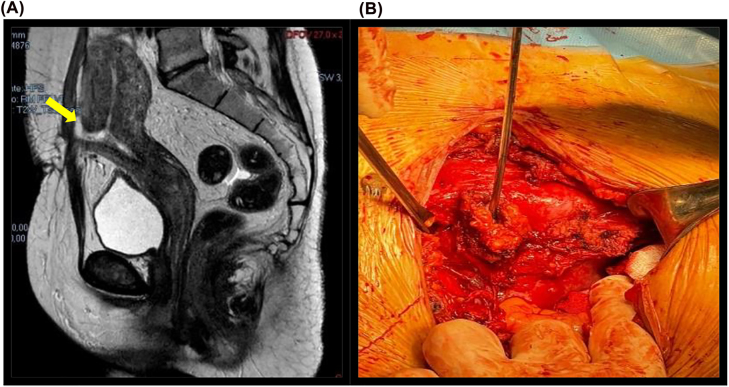

Objectives: The occurrence of a uterocutaneous fistula (UCF) as an uncommon and severe complication of caesarean section (CS). The aim of this study was to describe two cases of UCFs after CS and to discuss about symptoms, diagnosis and treatment.

Case presentation: Both women few days after CS had surgical site infection, fever and elevation of lab inflammation markers. bacterial culture of the wound drainage was positive for Escherichia Coli and Enterococcus Faecalis.

Conclusions: Fistula between uterine and skin is a rare condition but should be considered with signs of inflammation after cesarean section; 2D/3D ultrasound evaluation appears to be useful for diagnosis of UCFs when combined with CT fistulography and MRI in order to obtain early diagnosis and, consequently, a conservative surgery.